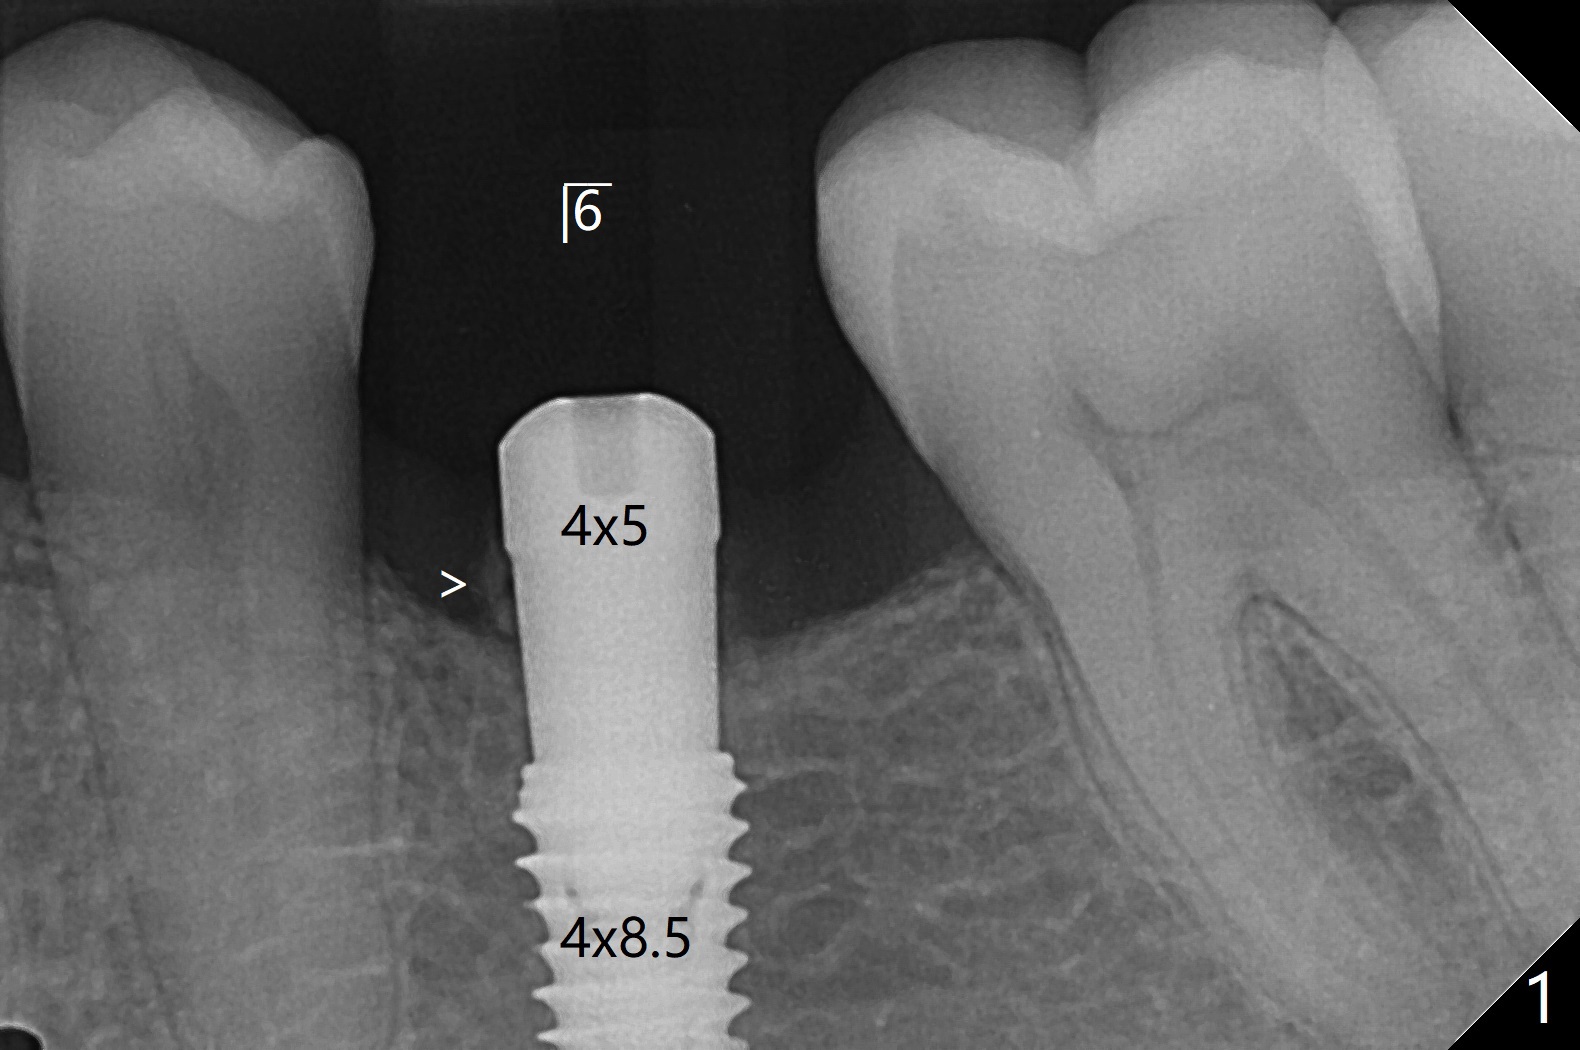

今天左下(图一,二),右下(图三)六种植,后者角化龈窄,事先做切口。两侧颊侧骨板均低,放置愈合基台后,在左下六基台和颊侧牙龈之间塞入骨粉(箭头),有点困难,应该事先做分离。而右下植骨在直视下进行,比较容易。

左下植体4毫米,放置4.5毫米愈合基台,不能就位,最后放置4毫米基台,完全入位(图一,二)。右下植体植入后,使用6毫米profile钻头,放置4.5毫米基台没问题(图三)。